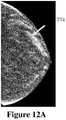

FIG. 12A shows the screen dump from the mp3 video at approximately the five (5) second time point, as represented inFIG. 9A, according to an embodiment of the invention; and

FIG. 10A shows the image of a human breast generated from a volumetric image reconstructed from a number of 2D X-Ray images produced by a DBT device, where the generated 2-D projection image was formed at a specific angle, where a micro calcification is occluded by denser breast tissue, as represented inFIG. 7A.FIG. 10B shows the generated 2-D projection image of the human breast formed from a different angle to that shown inFIG. 10A, where the micro calcification is visible and not occluded by the denser breast tissue, as represented inFIG. 7B.FIGS. 11A-11D show four (4) images which make up time points in the mp3 video of the dynamic comparison of the DBT of the right breast.FIG. 11A shows a screen dump from the mp3 video at a two (2) second time point, as represented inFIG. 8A.FIG. 11B shows a screen dump from the mp3 video at the five (5) second time point, as represented inFIG. 8B.FIG. 11C shows a screen dump from the mp3 video at the nine (9) second time point, as represented inFIG. 8C.FIG. 11D shows a screen dump from the mp3 video at the twelve (12) second time point, as represented inFIG. 8D.FIG. 12A shows an enlarged version ofFIG. 11B, the screen dump from the mp3 video at the five (5) second time point where theregion774 is identified, as represented inFIG. 9A.FIG. 12B shows an enlarged version ofFIG. 11C, the screen dump from the mp3 video at the nine (9) second time point where theregion774 is identified, as represented inFIG. 9B.